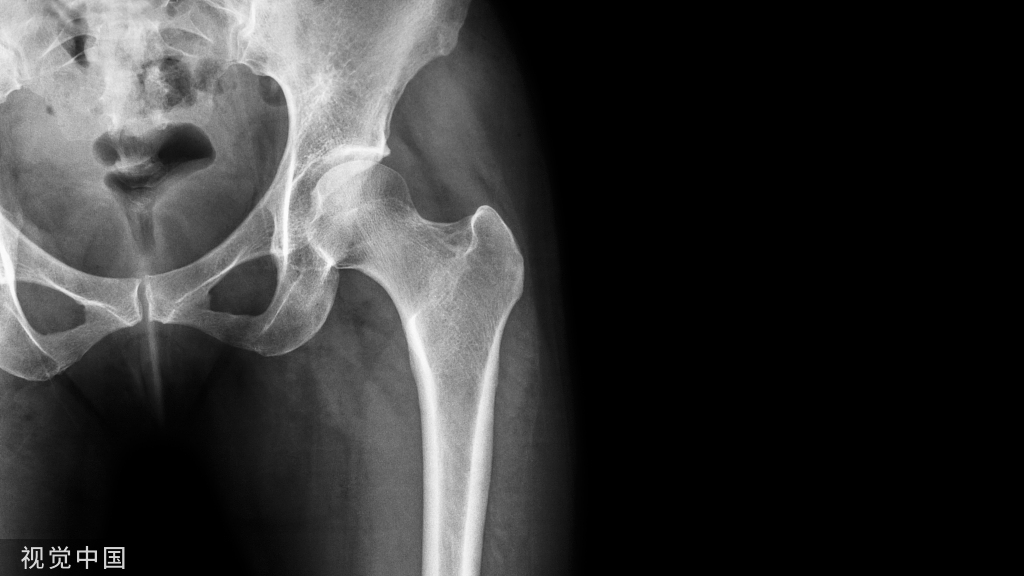

股骨粗隆间骨折PFNA内固定的技巧!

5.进针点:正位在大转子顶点,侧位在前中1/3交界处;进针方向:向内向前。

9.置入近端螺旋刀片:股骨颈内打入导针,透视确认位置(位置在股骨颈中点偏下远端到关节面下5-10mm),安装螺旋刀片。